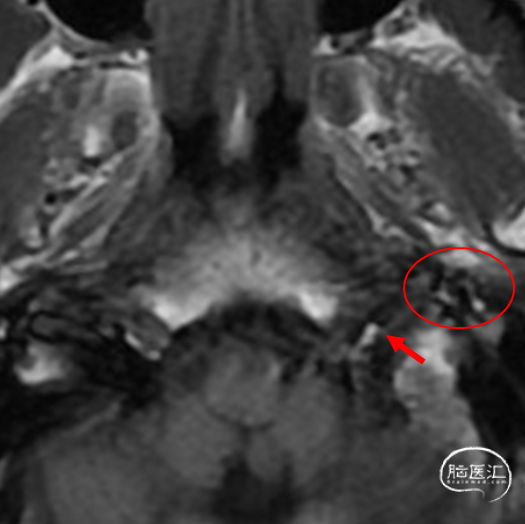

图3:头颅核磁平扫:左侧舌下神经管前方异常增粗的血管影(红箭:舌下神经管,红圈:异常血管团)。